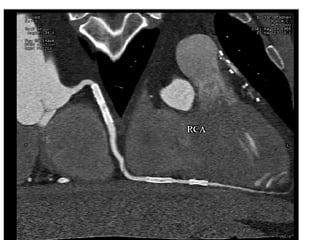

This document contains an ECG test with multiple questions and answers. It discusses cases of: 1. A 60-year-old patient with diabetes, hypertension and chest pain, showing an anterior STEMI with inferior ischemia. 2. A 55-year-old woman with shortness of breath and fatigue, showing a low-voltage ECG and echocardiogram revealing pericardial effusion due to severe hypothyroidism. 3. A 60-year-old with chest pain, showing an anteroseptal STEMI with diffuse ischemia.